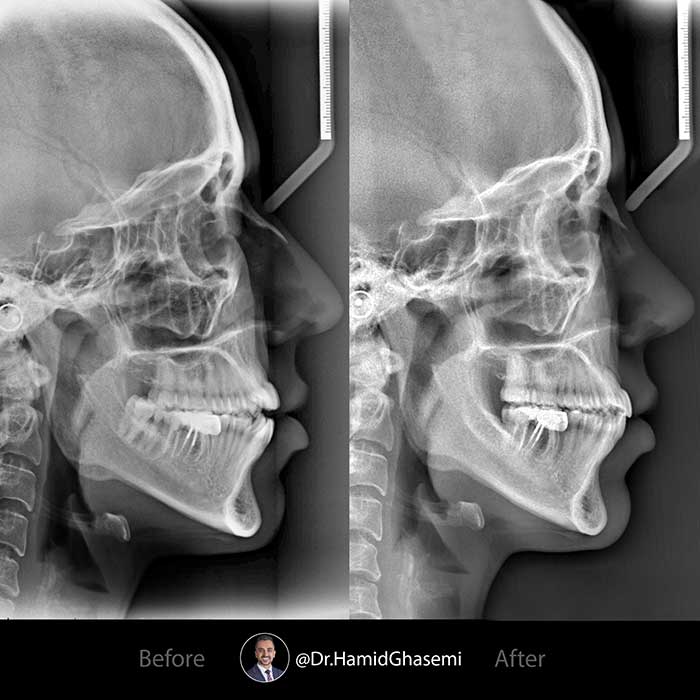

درمان ارتودنسی بدون جراحی فک در بیمار با ناهنجاری کلاس ۳ اپن بایت در مدت ۲۰ ماه با استفاده از تکنیک MEAW انجام شد. دندانهای عقل فک پایین جهت جابجایی و عقب بردن فک پایین کشیده شدند. اینتروژن دندانهای خلفی جهت بازسازی اکلوزال پلن و بسته شدن بایت انجام شد. به بهبود تحلیل لثه دندانهای خلفی بعد از درمان که به واسطه اینتروژن دندانهای خلفی میباشد دقت کنید.

Non surgical orthodontic treatment of class 3 openbite case done within 20 months using MEAW technique. Lower 3rd molars were extraceted in order to reposition lower arch posteriorly. Intrusion of posterior segment done to reconstruct occlusal plane and close the bite. Notice the improvement of gums recession on posterior teeth which is due to intrusion of posterior segment.